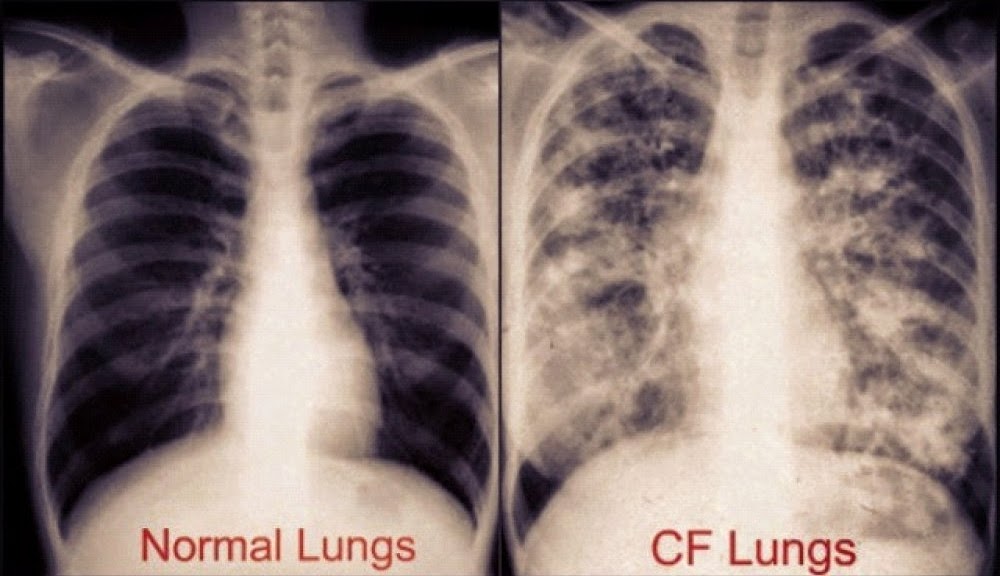

• charakteristické RTG zmeny (bronchiektázie, atelektázy, infiltráty…)